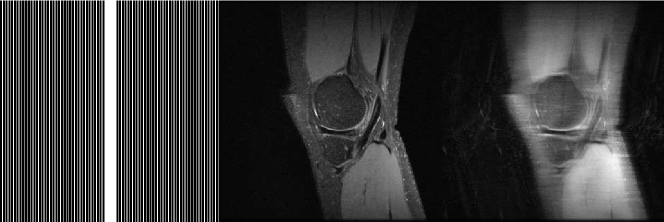

We use the fully sampled knee datasets from mridata.org to evaluate our RD-U-Net. There are 20 datasets, and the data were acquired in Cartesian coordinate on a GE clinical 3T scanner, with the following parameters: Receiver Bandwidth = 50.0, number of coils = 8, acquisition matrix size = 320 320, FOV = 160mm 160mm 153.6mm, number of slices = 256, TR = 1550ms, TE = 25ms, FA = 90, sequence type = SE. For each dataset, we only use the 150 slices from the central part (the 51st to 200th slices). We randomly pick 1 dataset for training, and 1 dataset for testing. For data augmentation, we generate 8 times more training samples by rotating and reflecting the images. The original k-space data are retrospectively down sampled by 4 times with 16 ACS (auto-calibration signal, 5% of total PE). The sampling pattern, a high resolution reconstructed image and a low resolution reconstructed image (by zero-filled) are shown in Fig. 4.

To determine the value of , we first test the our model with with 1 trial for each value, using the loss function stated in Eq. 3. We use the with the least MSE for the remaining experiments. The plot of the testing loss for different is in Fig. 3(a). To evaluate the performance of the RD-U-Net model, we compared the reconstruction results with GRAPPA [2] and U-Net [17]. Tab. 1 report the results for 5 different runs, and Fig. 5 illustrates sample visual results. For the zero-filled reconstruction, there exists a lot of aliasing artifacts (see Fig. 4(c)). Although GRAPPA removes the aliasing artifacts, the reconstructed image is still with a lot of noise (Fig.5(a)). The U-Net approach is better than GRAPPA, but the result is still lack of details (Fig. 5(b)). The proposed RD-U-Net provides a better reconstructed image with the presentation of residual dense block. In Fig.5(c), we can see that the result is sharper at the edges, and clearer for the details. The Fourier constraint is also useful for obtaining a better reconstruction, as shown in Fig. 3(b), adding the such regularization leads to lower MSE.

| (a) (b) (c) |